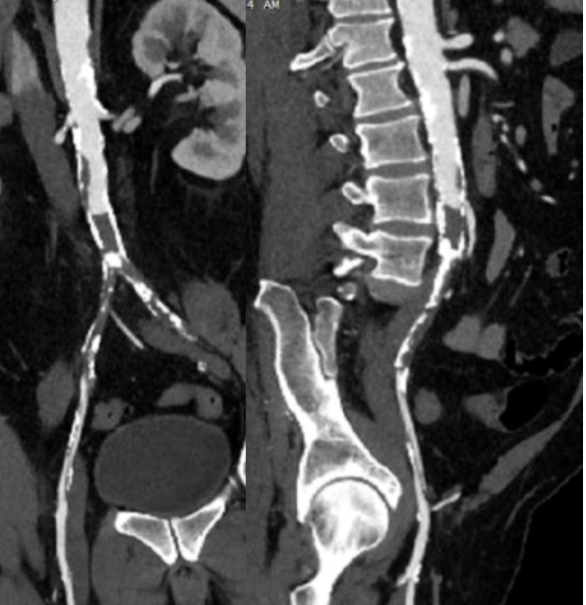

The patient was a 50 something year old man who I took care of in 2016 before I left for Abu Dhabi. He had a background of hypertension, hypercholesterolemia, and IDDM with chronic immunosuppression for rheumatoid arthritis. For several weeks he had rest pain in his feet and impending gangrene of his left great toe. More worrisome was the development of punched out ulcers on his groin crease resulting in weeping wounds after a bout of cellulitis. He had no palpable femoral pulses. Pulse volume recordings showed flat lines from the thigh to the feet.

CTA of the abdomen and pelvis with runoff showed aortic occlusion due to heavily calcified plaque with reconstitution of the external iliac arteries via the internal iliac arteries. The common femoral arteries were only mildly diseased and there was patent runoff.

Centerline up right femoral into aorta shows occluded aorto-iliac segment and diseased external iliac artery.

Centerline up left femoral into aorta shows mirror image of disease on left side

In the five years since the operation, he has needed an SMA stent and has devloped worsening CKD and autoimmune diseases. But one of the gratifying things is he healed his wounds on this groins and thighs and the left hallux, and pain has never recurred. He had a contrast CT at the 5 year point (figure) showing a widely patent graft, and he sought me out when he heard that I was back in Cleveland.